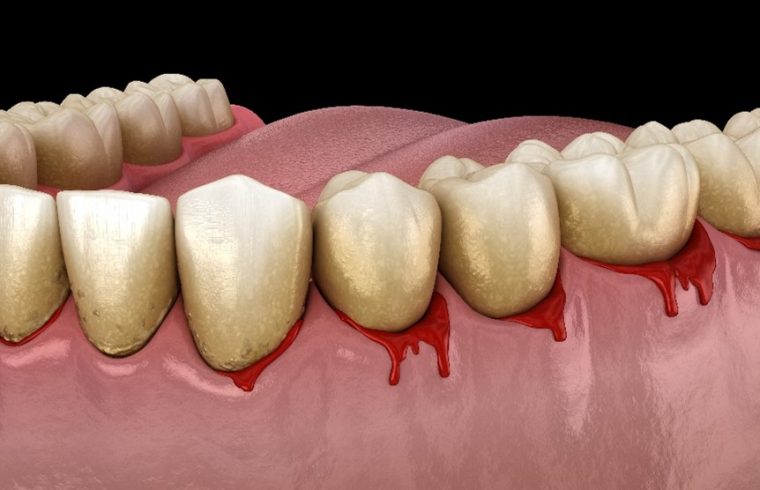

歯ぐきから出血をしているイメージイラスト

歯周病とは、歯と歯ぐき周りの組織に炎症が起こる慢性的な口腔疾患の一つです。歯周組織が炎症を起こし、歯の周りの歯ぐきや歯を支えている骨が溶けてしまう病気です。進行すると歯と歯ぐきの間に深い溝(歯周ポケット)ができます。歯周ポケットの中で細菌が増殖し、歯周病はさらに悪化します。

細菌が食べかすなどを分解する過程で強い臭いがするガスが発生するため、口臭の原因にもなります。